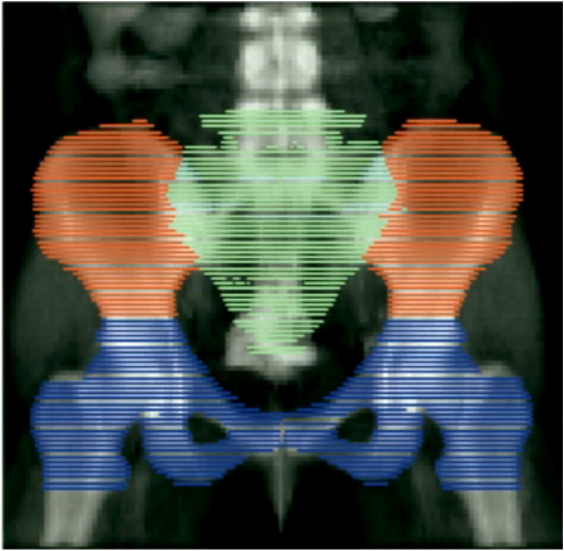

Lee AY, Bazan JG, Pelizzari CA, Chang DT, Liauw SL Lower Pelvis Bone Marrow Dose Constraints to Reduce Hematologic Toxicity in the Treatment of Anal Cancer. Int J Radiat Oncol Biol Phys. Sept 2014; Vol 90, Issue 1, Supplement, S33.